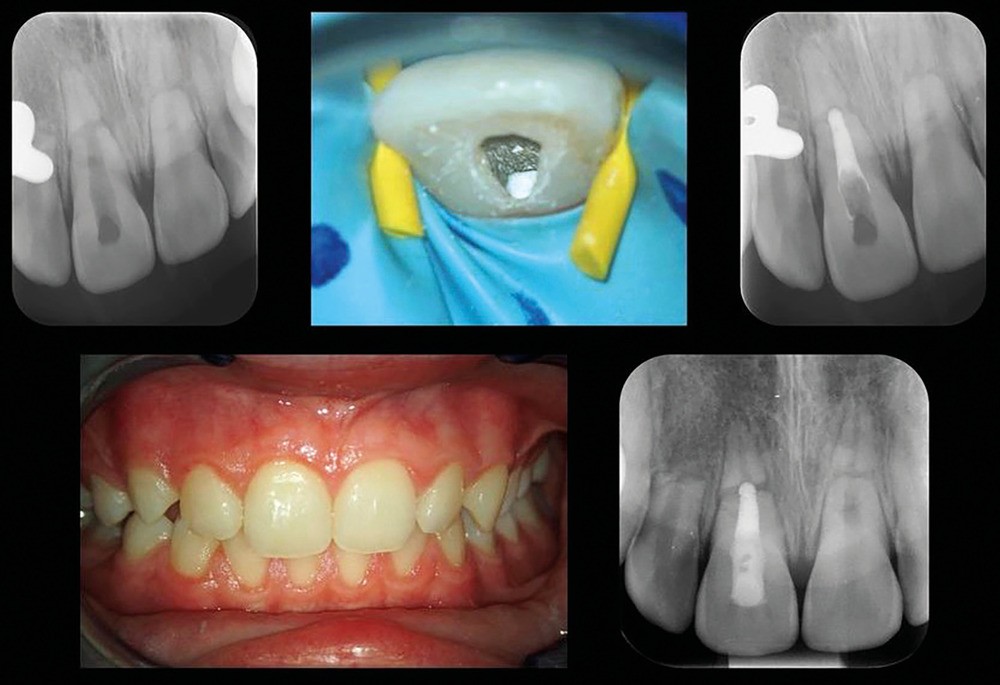

Dans cet exemple, le suivi du cas est essentiel, comme pour tous les cas de traumatologie dentaire. Ici, une prise en charge endodontique de la 11 a été nécessaire quelques mois après la dépose de la contention. Le suivi clinique a guidé cette décision thérapeutique. La 11 ne répondait plus aux tests de sensibilité pulpaire (test de sensibilité thermique au froid et test électrique négatifs), la dent présentait également une décoloration coronaire et une sensibilité à la percussion indiquant que la pulpe de la 11 était nécrosée.

Cette nécrose faisant suite à une fracture corono-radiculaire complète et une luxation du fragment coronaire, il était recommandé de réaliser au moins une séance de temporisation à l’hydroxyde de calcium, avant d’obturer définitivement le canal radiculaire à l’aide d’un matériau dit « bioactif ». Dans ce cas-ci, du RRM putty a été utilisé, avant de placer un composite dans la chambre pulpaire, durant la même séance (fig. 5).